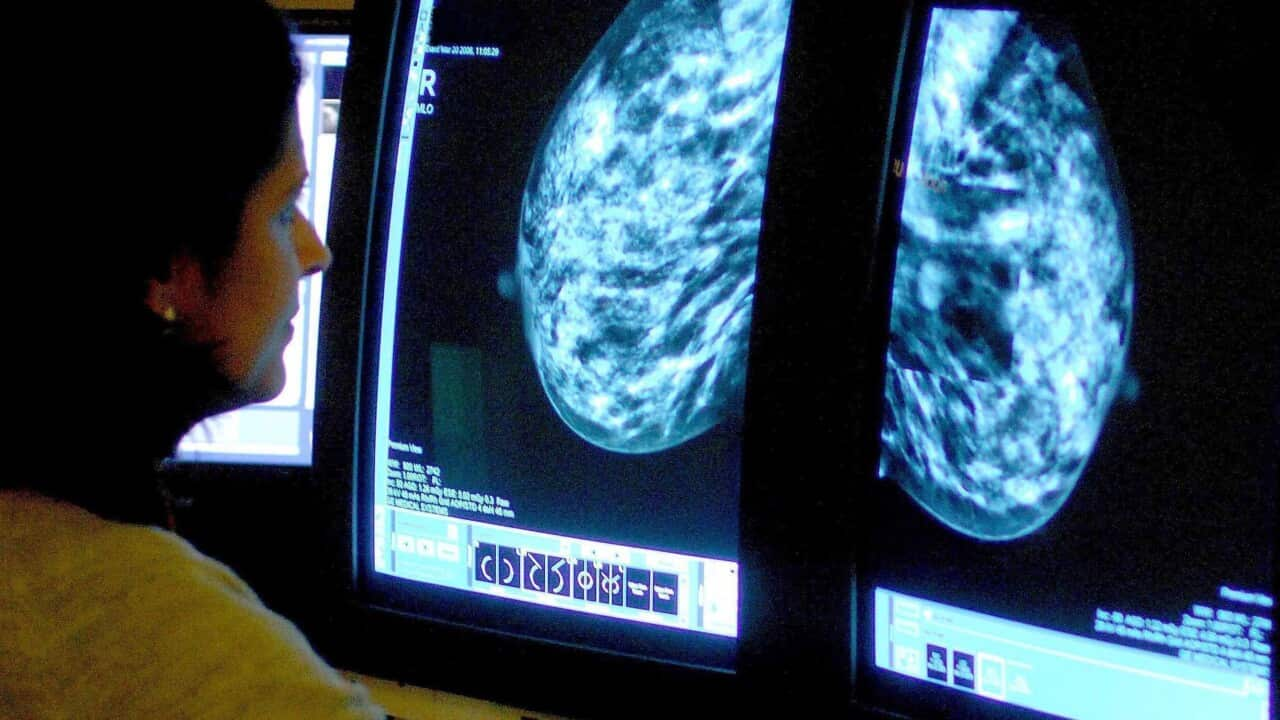

وقارنت دراسة أجراها معهد السرطان في نيو ساوث ويلز يوم الخميس متوسط حجم الورم لدى النساء اللواتي تأخر فحص التصوير الشعاعي للثدي لديهن بسبب الوباء وأولئك اللواتي لم يقمن بذلك.

بالنسبة للسيدات اللواتي انتظرن الاختبار، كان متوسط حجم الورم 16.2 ملم، مقارنة مع 15.9 ملم للواتي لم يفعلن ذلك.

وخلص الباحثون إلى أن الاختلاف البالغ 0.3 ملم ليس خطيراً من الناحية الطبية، وأنه من المحتمل أن تتجاوز أي مخاطر إضافية على فوائد الحد من عدوى كوفيد في حينه.

وكتب الباحثون: "تحليلاتنا بأثر رجعي لم تظهر أي دليل على تغيير جوهري في حجم الأورام".